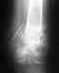

Мне 38 лет вес 74кг прошло 3 месяца после операции добавляю последний снимок от 1го февраля посмотрите пожалуйста.